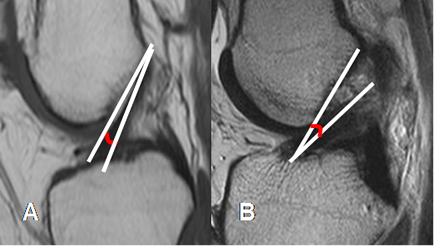

Fig 15. LCA normal.

A: RM sagital en T1. Relación normal, con el platillo tibial.

B: RM sagital en T2. Ruptura del LCA, el cual está horizontalizado y con disminución del ángulo.